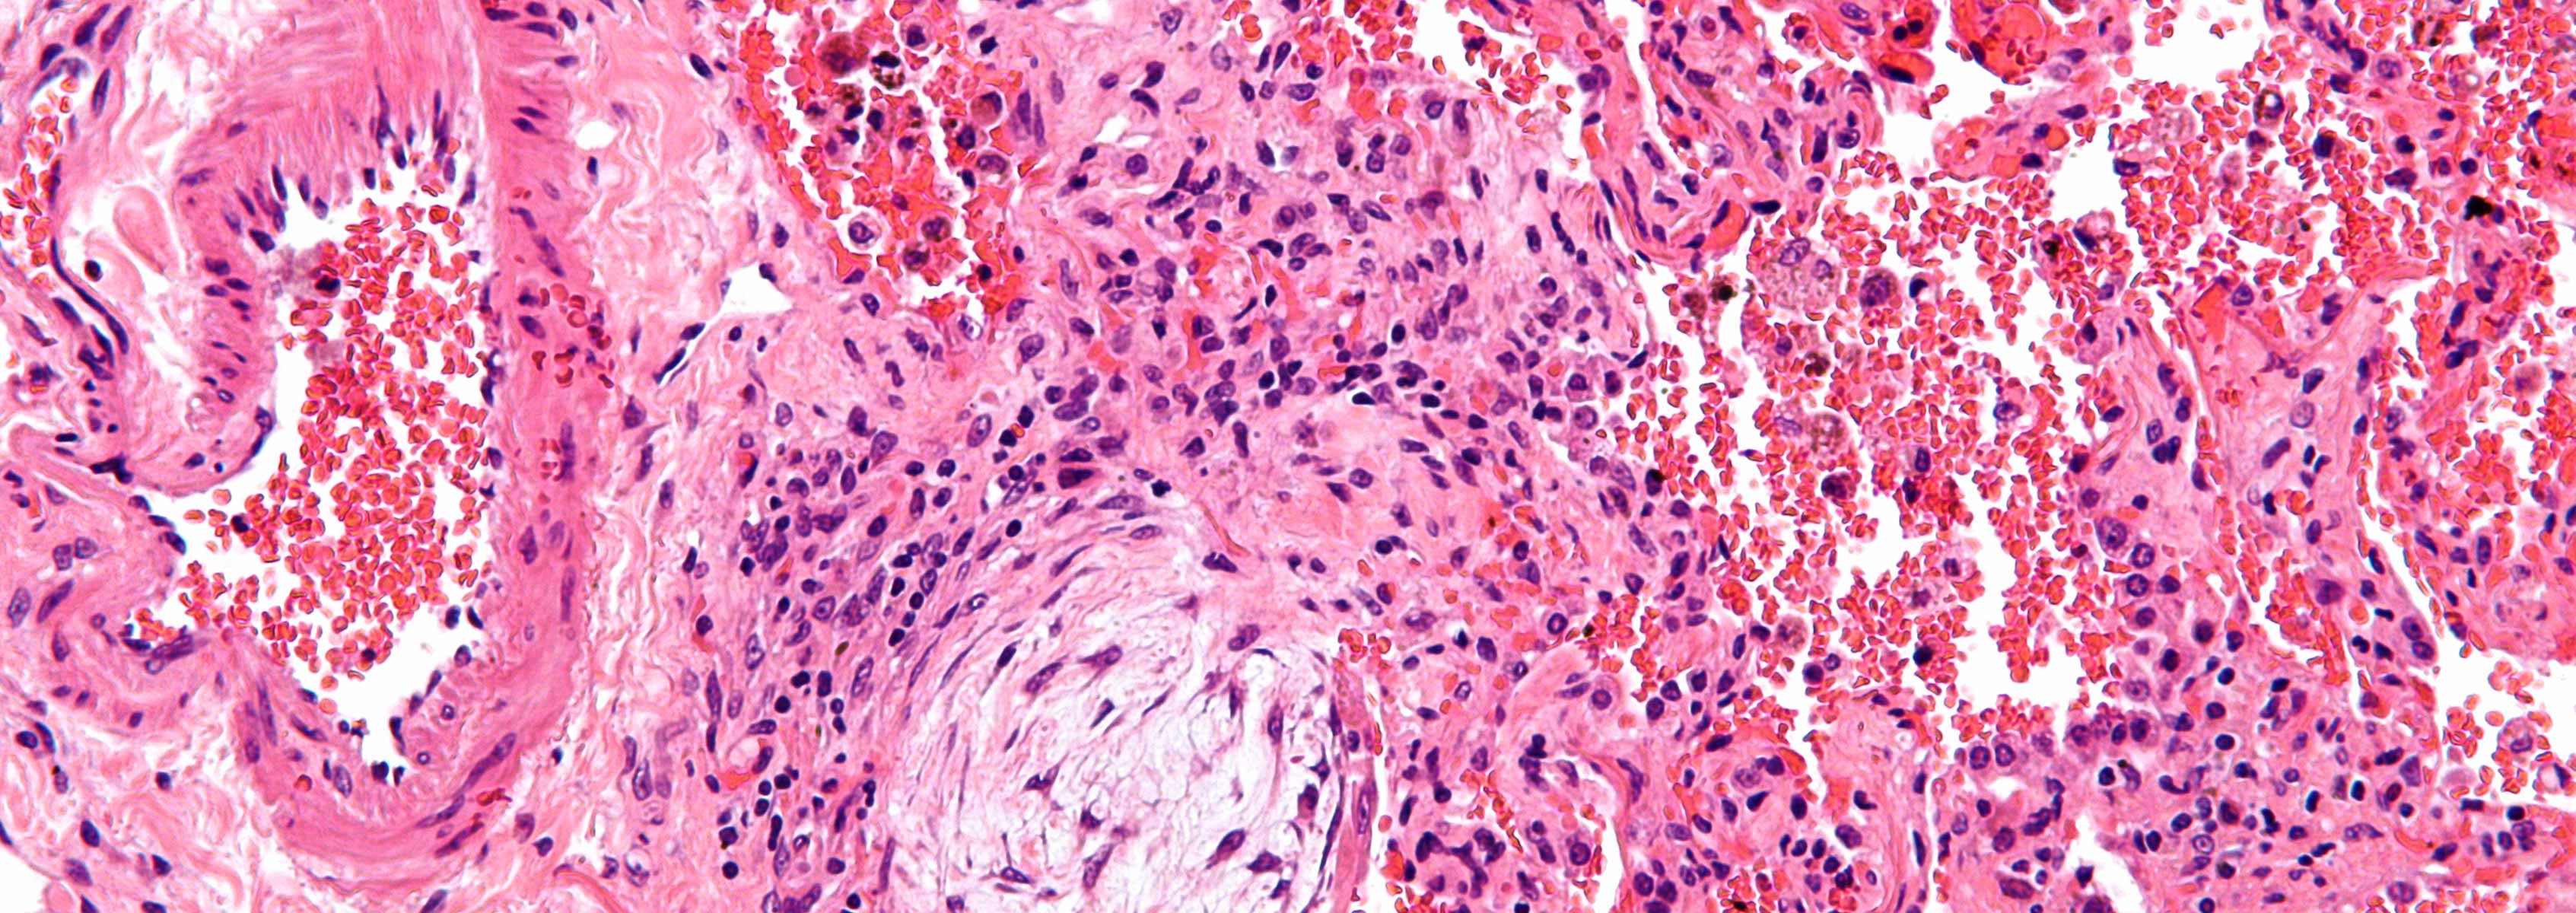

Pneumonia is a leading cause of death following lung transplantation. Guidelines endorse a diagnosis of tracheobronchitis rather than pneumonia for lung transplant recipients with signs and symptoms consistent with respiratory tract infection and positive cultures, and in whom there are no new or progressive lung parenchymal findings. However, conclusive pathologic evidence for tracheobronchitis among lung transplant recipients is lacking, and it is unclear if this diagnosis constitutes a coherent disease entity. Since diagnostic criteria for pneumonia and tracheobronchitis following lung transplantation are non-specific, it is often difficult to distinguish respiratory tract infections from colonization in the absence of disease or from non-infectious conditions like acute cellular rejection or chronic rejection due to bronchiolitis obliterans syndrome. Respiratory tract cultures may be positive with each of these diseases.

DNA sequencing-based microbiome profiling studies have demonstrated that the lower respiratory tract harbors complex microbial populations. Recent data indicate that pneumonia is characterized by loss of microbial diversity and emergence of a dominant pathogen. Specific members of the lung microbiota have been shown to stimulate discrete immune cell populations, and to correlate with general indicators of inflammation in lung transplant and non-lung transplant populations. Microbiome and inflammatory markers that distinguish between pneumonia, tracheobronchitis and respiratory tract colonization are undefined.